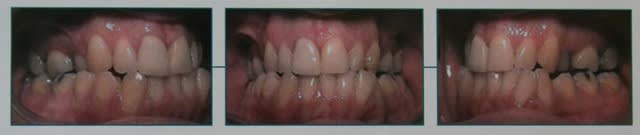

Finalement, j’ai quand même suivi les conseils du professeur et fait extraire les quatre premières prémolaires de ce garçon

P.S. : j’ai remis les photos ci-dessous.

Je ne peux pas te le montrer terminé car je vais commencer le traitement seulement maintenant. Les premières prémolaires viennent seulement d'être extraites.

Je me suis rappelé les arguments du professeur qui mettait en avant l’incompétence labiale de ce jeune homme, sa béance, la quantité d’encombrement antérieur inférieur ingérable à cause de la largeur d’arcade postérieure quasi normale… et son expérience clinique.

Et comme il disait qu’il fallait extraire les premières prémolaires, je lui fais confiance, c’est tout.

Moi, je ne le pense pas. Cependant, comme il manque peu de chose à cette arcade, j’étais plutôt tenté d’extraire les secondes prémolaires que les premières pour obtenir autant une mésialisation des dents postérieures qu’un gain de place pour le groupe incisivo-canin et ainsi ne pas prendre le risque de créer un recul des lèvres en fermant les espaces d'extraction.

Finalement, je me suis quand même rallié à l’avis (l’expérience) du professeur et fait extraire les premières prémolaires.

En réfléchissant, je me demande maintenant si ce n’est pas à cause de sa culture edgewise (qui ne va pas dans la nuance) qu'il m’a dit d’extraire les premières plutôt que les secondes prémolaires et j’ai un petit peu peur du résultat.